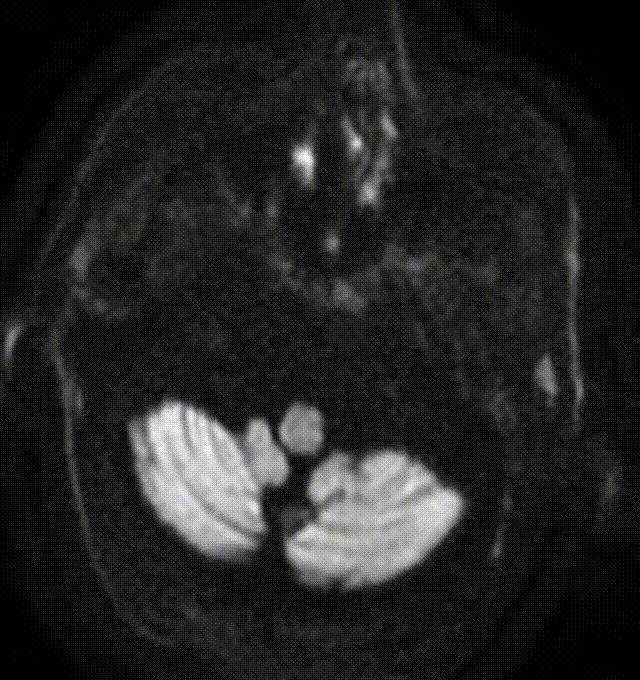

患者突发意识模糊,四肢僵硬,急诊MR DWI+MRA提示基底动脉闭塞,右椎主供血。

术前DWI +MRA